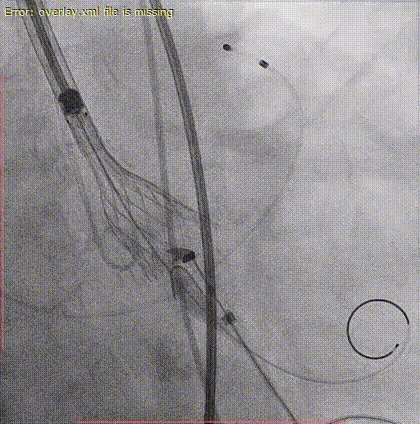

术前冠脉造影

主动脉根部造影

22mm球囊预扩,些许腰征,无瓣周漏,未见冠脉阻挡。(决定使用Taurus Elite AV26瓣膜)

瓣膜定位

瓣膜第一次释放(位置不理想,出现瓣周漏)

利用可回收功能重新定位释放

瓣膜完全释放(受钙化影响,瓣架形态挤压明显,决定球囊后扩张)

22mm球囊后扩

球囊后扩后,瓣架形态改善明显,造影无瓣周漏、无反流